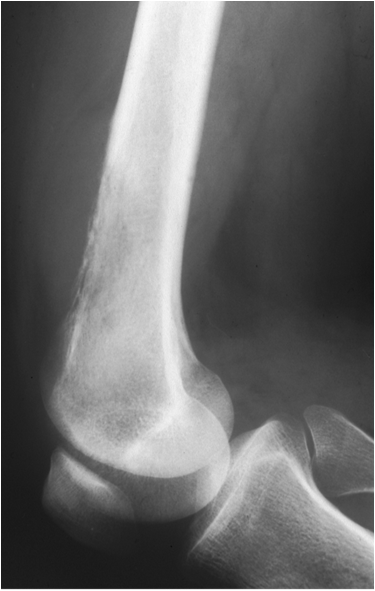

Fig. 18. An osteosarcoma is seen as an ill-defined lesion with a permeative pattern of bone destruction with cortex involvement in the distal metaphysis of the femur.